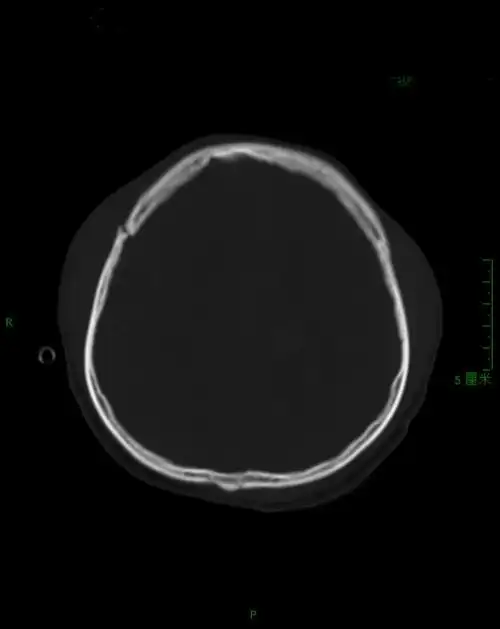

右侧额骨骨折

额部开放凹陷性骨折